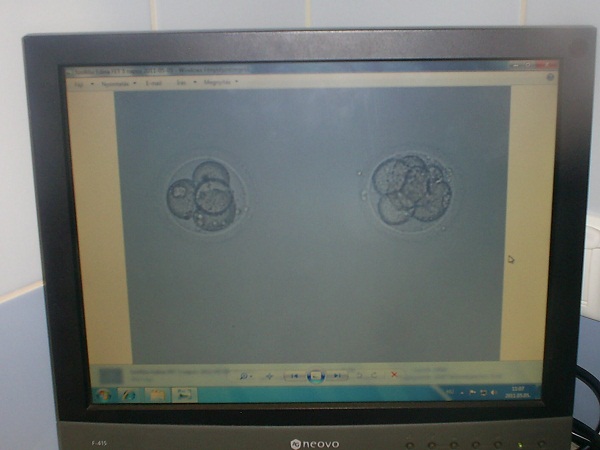

Etnám! Jól takaríts ám ki, nem ám nem bírsz majd megüli a seggeden a beülti után. Nagyon örülök, hogy Norbinál rendeződnek a dolgok. Én is azt mondom, amit a többiek, hogy szerintem most már igen is keressen valami jó melót. Lehet, hogy most elsőre nem olyan jó a pénz, de lehet, hogy korrekten be lesz jelentve és később ha beindul a szezon, és meglesznek vele elégedve emelnek a pénzén. Én biztosan nem díjaznám, ha a párom itthon hagyna a két gyerekkel, és elmenne ilyen hajós melóra. Ez annak jó, akinek se kutyája, se macskája! Lehet, hogy a pénz nagyon jó, de szerintem nem ér annyit, hogy ti közben elhidegüljetek tőle, és hogy a gyerek megkérdezze az apjától, hogy ki ő... Én ismerek ilyet, pedig ő csak építkezett reggeltől estig építette a saját házukat, és a kisebbik gyerek egyszer megkérdezte, amikor éjjelre ment dolgozni, hogy mész haza aludni, mert olyan keveset látta az apját. Na a palinak nem kellett több mondanom sem kell. Onnantól lassabban ment az építkezés... (Mindent ő maga csinált és 3 év alatt költözött be!!) Szóval jól gondoljátok meg, mert ebbe neked is van beleszólásod Drágám! Holnap reggelre megy a drukk! 2-en lesznek vissza ültetve?? Anyám, 2 kis Boti!!